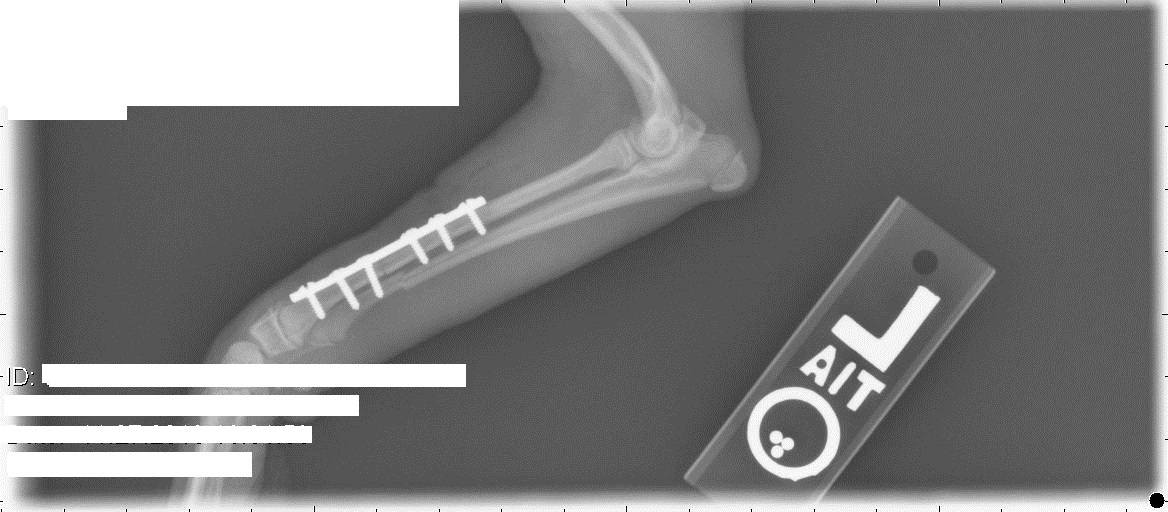

Ну да, у нас тоже счастливо скакала. И вот на чем: (первый снимок сделан перед операцией, после снятия гипса)

Сходили снова к вету, сняли повязку. Лапа выглядит нормально, собака на нее понемногу наступает. Про зону роста вет сказал, что она начинается на несколько миллиметров после последнего болта. Пластину все-таки будут снимать через какое-то время. В общем-то, принципиально это тот же аппарат Илизарова с поперечными винтами, только внутри. Локтевую кость не скрепили, сказали, что без надобности.